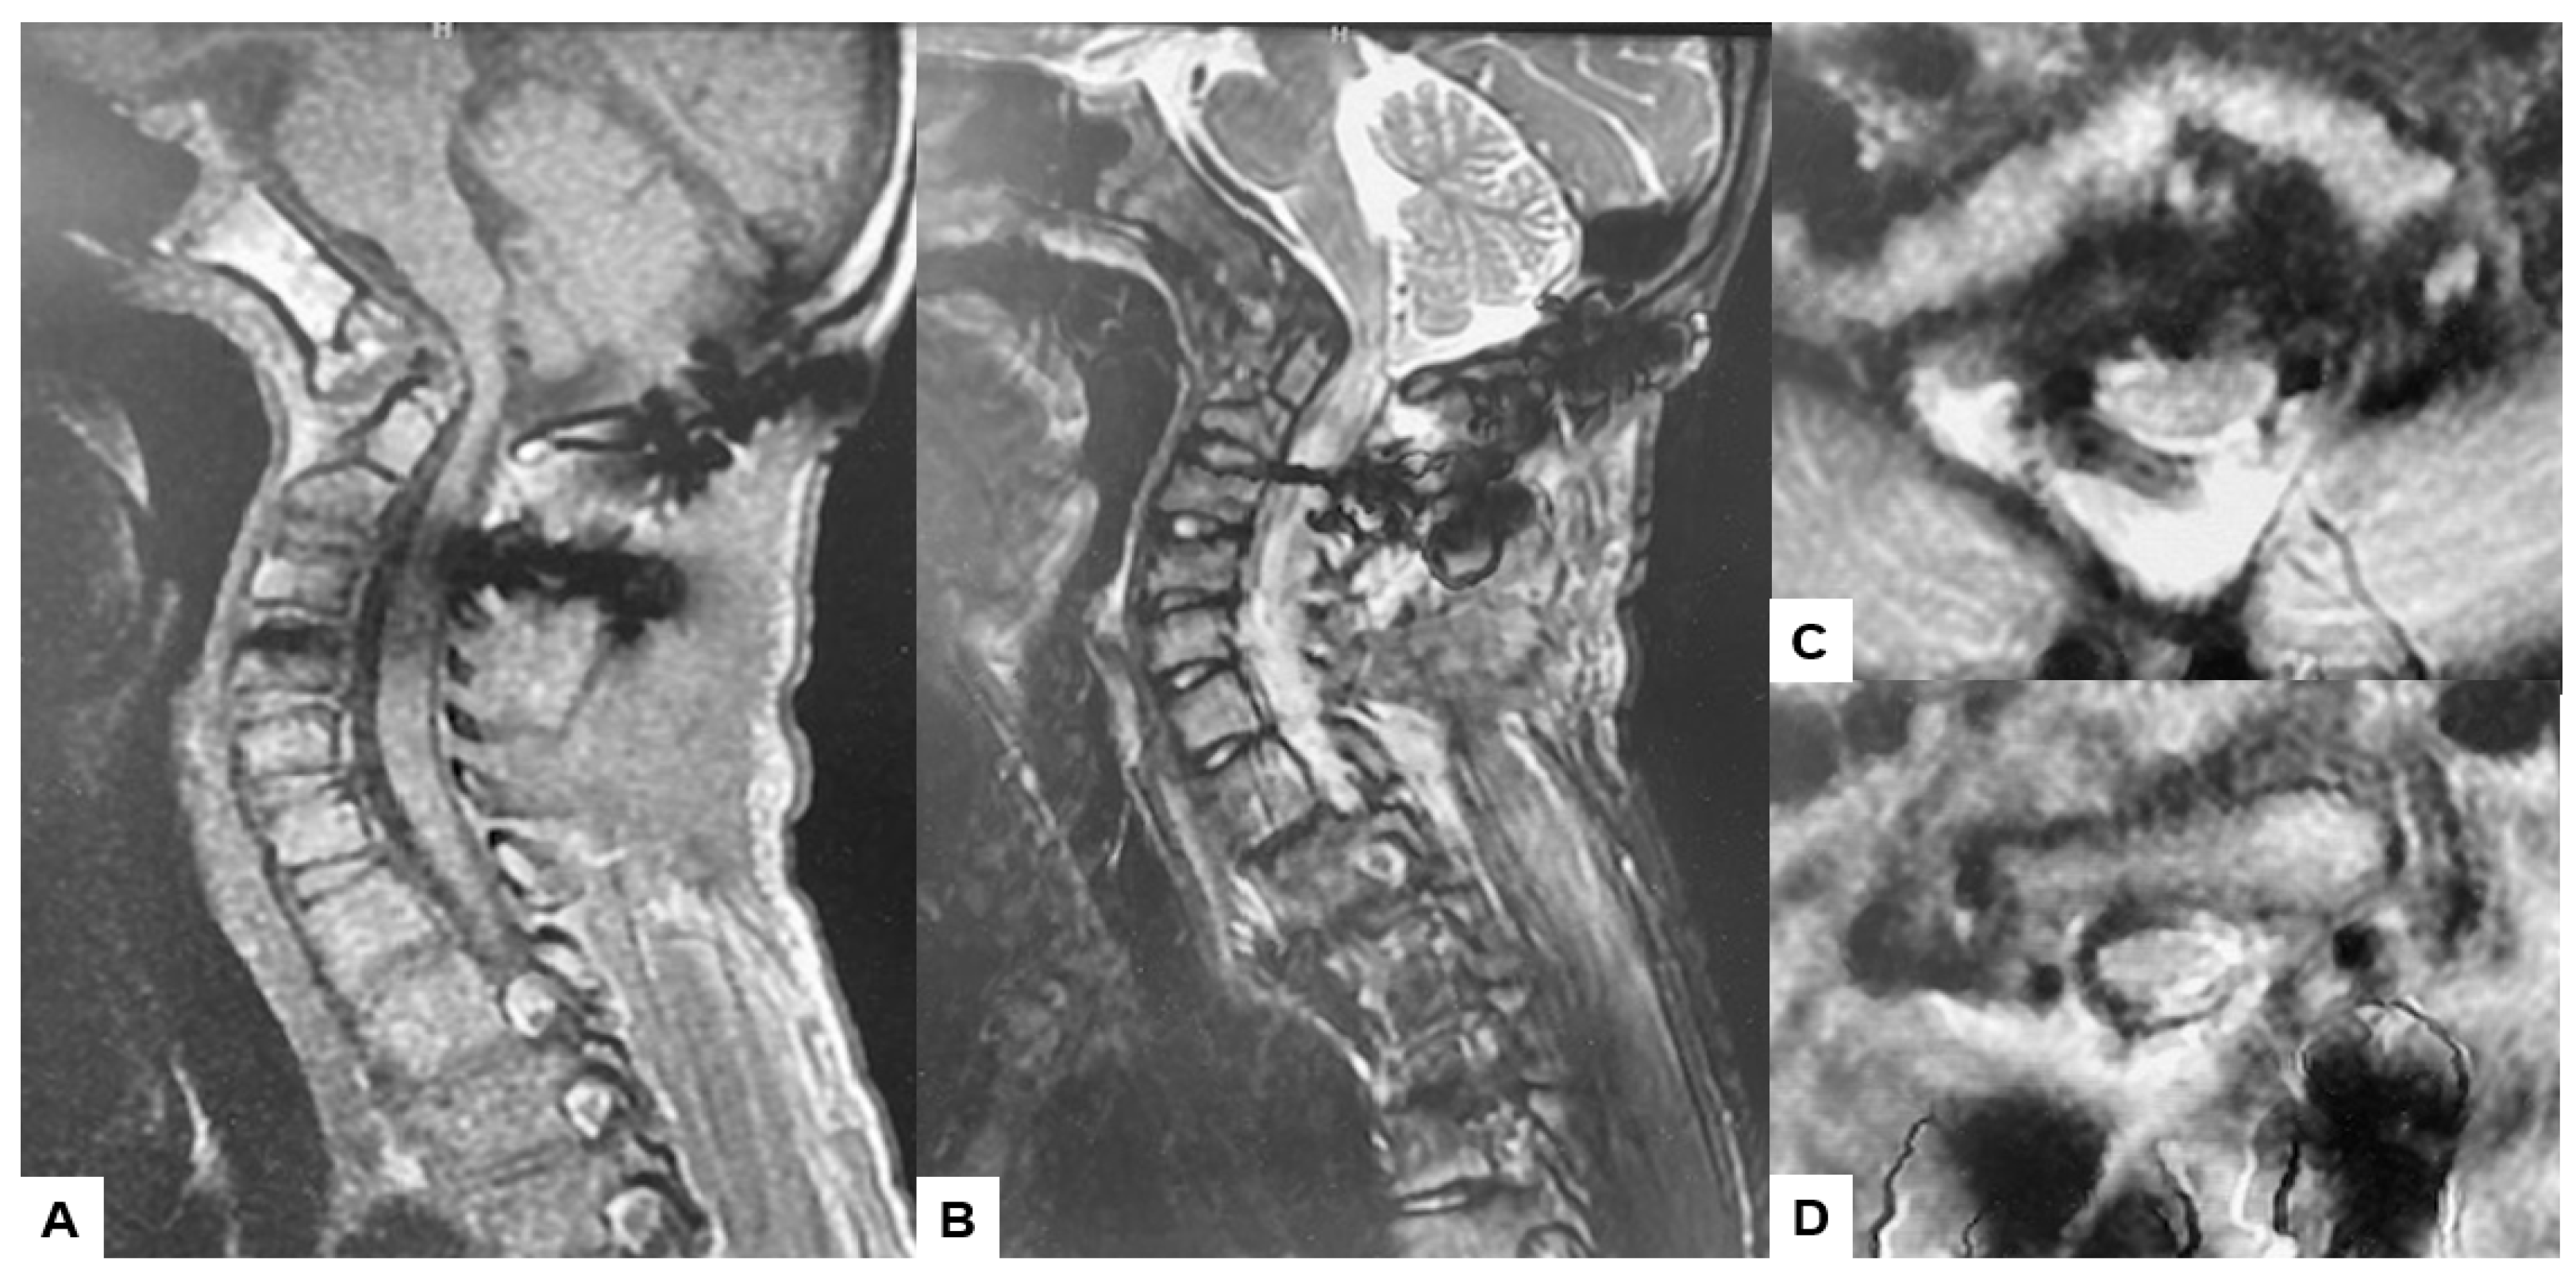

Preoperative cervical radiographs revealed a short neck and a C2/3 fusion anomaly. Dens protrusion into the foramen magnum measured 9.4 mm above McGregor’s line and 4.2 mm above McRae’s line, with an anteroposterior (AP) diameter of the foramen magnum measuring 10.7 mm (Figure 2). Preoperative magnetic resonance imaging (MRI) depicted severe compression of the cervicomedullary cord by the dens, with a cervicomedullary angle (CMA) measuring 116 degrees (Figure 3).

Figure 3.

Preoperative MR imaging, (A) T1 weighted mid-sagittal MR imaging, (B) T2 weighted mid-sagittal MR imaging, (C) T2 weighted axial MR imaging at C1, (D) T2 weighted axial MR imaging at C1-2, (E) T2 weighted axial MR imaging at C2, (F) T2 weighted axial MR imaging at C3. The spinal cord was compressed severely due to basilar invagination. The red arrows show severe compression of the cervicomedullary cord by the dens.

Postoperative MRI indicated excellent spinal cord decompression (Figure 15).

Figure 15.

Follow-up images, (A) Mid sagittal T1-weighted MR imaging, (B) Mid sagittal T2-weighted MR imaging. (C) Axial T2-weighted MR imaging at C1, (D) Axial T2-weighted MR imaging at C2. The spinal cord was adequately decompressed.